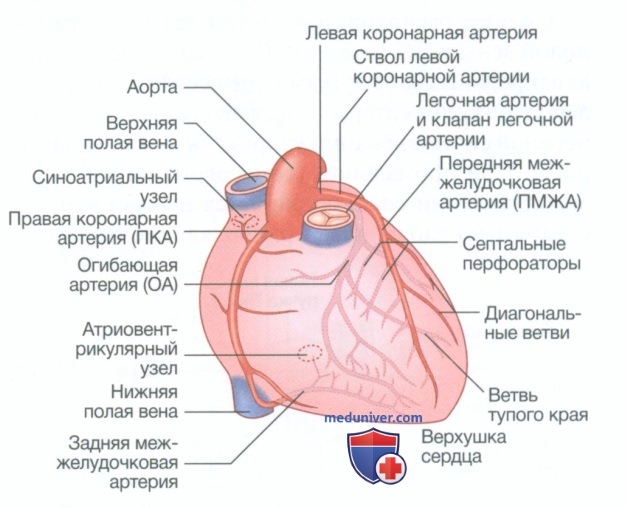

Анатомия коронарных артерий: КТ-изображения